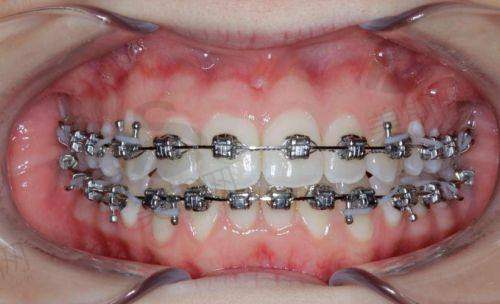

2. 数字化牙齿矫正:采用进口iTero口内扫描仪,3分钟获取牙齿数据,通过3D模拟系统提前展示矫正过程及更终成效,支持传统金属托槽、自锁托槽、陶瓷半隐形、时代天使/隐适美隐形矫正等多种方案。

依托数字化矫正平台,医院实现“数据采集 - 方案设计 - 成效预知 - 全程监控”全流程数字化管理。患者就诊时通过iTero口内扫描仪替代传统硅橡胶取模,避免恶心不适,数据即时上传至矫正设计系统,医生联合计算机算法制定方案,并通过3D动画展示每一步牙齿移动过程,患者可直观了解矫正成效并参与方案调整。矫正过程中,医生通过远程监控系统跟踪牙齿移动情况,及时调整矫治力,确保矫正周期缩短15% - 20%,精细度提升30%。

治疗方案:采用隐适美隐形矫正,通过iTero扫描模拟矫正成效,佩戴矫治器18个月。

患者反馈:“选择众植齿科就是看中他们的数字化矫正技术,一开始还担心成效,没想到医生给我看了3D模拟动画,每一步变化都清清楚楚。矫正过程中医生定期跟踪调整,现在牙齿整齐了,侧脸线条也变好看了,同事都说我像换了个人,自信心提升了不少!”